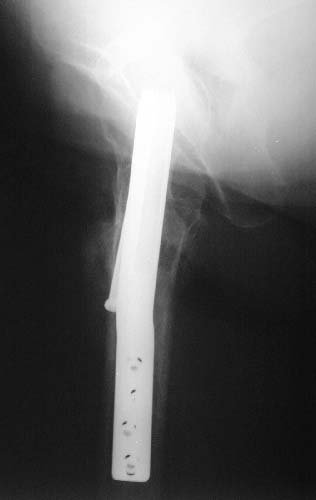

Does anyone on the list know of any references regarding the placement of cannulated hip screws above/below the lesser trochanter as it relates to the risk of subsequent subtroch fracture? i know placement should be above the lesser trochanter but i have been unable to find evidence to support this. thank you.

Reported 20% incidence of fracture if screws are placed too low, below the lesser trochanter, or  with un-filled drill holes there too. I have not looked at it in a long time but I believe the reference on this topic is: Karr, Clin Ortho Rel Res 1985.